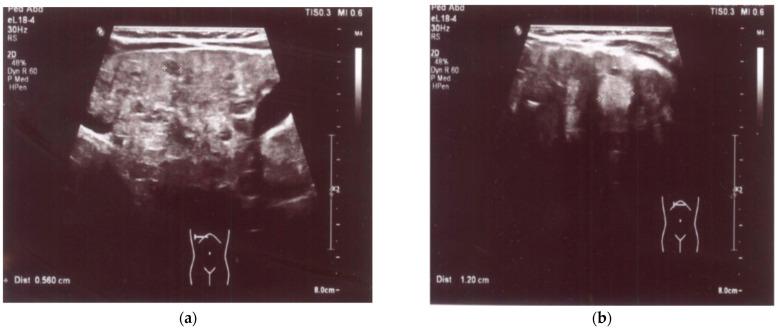

Hereditary type 1 tyrosinemia (HT1) is a rare inherited autosomal recessive disorder of tyrosine metabolism, characterized by progressive liver damage, dysfunction of kidney tubules, and neurological crises. In the course of this disease, due to the deficiency of the enzyme fumarylacetoacetate hydrolase (FAH), toxic intermediate metabolites of tyrosine breakdown, such as fumarylacetoacetate (FAA), succinylacetoacetate (SAA), and succinylacetone (SA), accumulate in liver and kidney cells, causing cellular damage. Because of this, an increased SA concentration in the blood or urine is pathognomonic of HT1. In the year 2000, HT1 was diagnosed in Lithuania for the first time, and this was the first time when a specific treatment for HT1 was administered in the country. Over two decades, four cases of this disease have been diagnosed in Lithuania. In the first of these patients, the disease was diagnosed in infancy, manifesting as liver damage with liver failure. Treatment with nitisinone was initiated, which continues to be administered, maintaining normal liver function. Liver transplantation was performed on two subsequent patients due to complications of HT1. It is crucial to diagnose HT1 as early as possible in order to reduce or completely eliminate complications related to the disease, including progressive liver failure and kidney dysfunction, among others. This can only be achieved by conducting a universal newborn screening for tyrosinemia and by starting treatment with nitisinone (NTBC) before the age of 1 month in all cases of HT1. However, in those countries where this screening is not being carried out, physicians must be aware of and consider this highly rare disorder. They should be vigilant, paying attention to even minimal changes in a few specific laboratory test results-such as unexplained anemia alongside neutropenia and thrombocytopenia-and should conduct more detailed examinations to determine the causes of these changes. In this article, we present the latest clinical case of HT1 in Lithuania, diagnosed at the Children's Diseases' Clinic of the Lithuanian University of Health Sciences (LUHS) Hospital Kaunas Clinics. The case manifested as life-threatening acute liver failure in early childhood. This article explores and discusses the peculiarities of diagnosing this condition in the absence of universal newborn screening for tyrosinemia in the country, as well as the course, treatment, and ongoing monitoring of patients with this disorder.

遗传性酪氨酸血症 1 型(HT1)是一种罕见的常染色体隐性遗传酪氨酸代谢紊乱疾病,其特征为进行性肝损伤、肾小管功能障碍和神经危象。在该疾病的病程中,由于酶延胡索酰乙酰乙酸水解酶(FAH)的缺乏,酪氨酸分解的有毒中间代谢物,如延胡索酰乙酰乙酸(FAA)、琥珀酰乙酰乙酸(SAA)和琥珀酰丙酮(SA),在肝和肾细胞中积累,导致细胞损伤。正因为如此,血液或尿液中 SA 浓度的增加是 HT1 的特征性表现。2000 年,立陶宛首次诊断出 HT1,这也是该国首次对 HT1 进行特定治疗。在过去的二十多年里,立陶宛共诊断出 4 例该疾病。在这些患者中的第一个患者中,疾病在婴儿期被诊断出来,表现为肝损伤和肝功能衰竭。开始使用尼替西农进行治疗,目前仍在继续使用,以维持正常的肝功能。由于 HT1 的并发症,对随后的两名患者进行了肝移植。早期诊断 HT1 至关重要,以减少或完全消除与疾病相关的并发症,包括进行性肝功能衰竭和肾功能障碍等。只有通过对酪氨酸血症进行普遍的新生儿筛查,并在所有 HT1 病例中在 1 个月龄之前开始使用尼替西农(NTBC)治疗,才能实现这一目标。然而,在那些未进行这种筛查的国家,医生必须意识到并考虑到这种非常罕见的疾病。他们应该保持警惕,注意几个特定实验室检测结果的微小变化,例如原因不明的贫血伴有中性粒细胞减少和血小板减少,并进行更详细的检查以确定这些变化的原因。本文介绍了立陶宛大学健康科学大学医院考纳斯临床儿童疾病诊所最新诊断的 HT1 临床病例。该病例在儿童早期表现为危及生命的急性肝功能衰竭。本文探讨和讨论了在该国未进行普遍新生儿酪氨酸血症筛查的情况下诊断这种疾病的特点,以及该疾病患者的病程、治疗和持续监测。